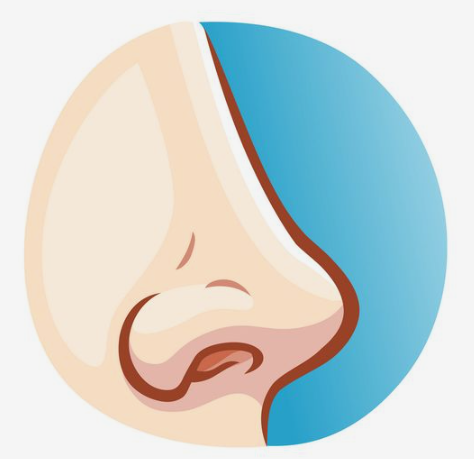

رینوپلاستی مدرن و جراحی زیبایی بینی کلاسیک

در این مقاله از وب سایت فوق تخصص جراحی پلاستیک و زیبایی و بهترین متخصص زیبایی در تهران “دکتر مهدی جعفری” با ما همراه باشید تا با رینوپلاستی مدرن و تفاوت های آن با جراحی زیبایی بینی کلاسیک آشنا شوید.

ترمیم جراحی زیبایی بینی

در این مطلب با فوق تخصص جراحی پلاستیک و زیبایی و بهترین جراح زیبایی دکتر مهدی جعفری همراه باشید تا با چگونگی ترمیم جراحی زیبایی بینی و عمل بینی یا رینوپلاستی آشنا شوید.

جراحی زیبایی بینی گوشتی و استخوانی و تفاوت های آنها

برای اینکه برآمدگی و نقایص بینی های استخوانی را بتوان از بین برد از غضروف ها و استخوان های بینی برداشته می شود و پس از ایجاد شدن شکاف ها، پوست توسط جراح بینی بلند شده و جراح بینی می تواند به استخوان ها و غضروف ها دسترسی پیدا کند. برآمدگی هایی که در بینی های استخوانی وجود دارد با توجه به تشخیص متخصص زیبایی با یک ابزاری شکسته می شود و یا اینکه جراح آن را با سمباده هایی مخصوص شکل می دهد تا بتواند دقت بیشتری را در از بین بردن بخش های زائد داشته باشد.

پوست بینی و نقش آن در جراحی بینی

درست است که در جراحی زیبایی بینی یا رینوپلاستی پوست هیچ تغییری نخواهد کرد ولی در نتیجه جراحی تاثیر به سزایی دارد. معمولا جراحی افراد با پوست های نازک و یا خیلی ضخیم نتیجه ی خیلی راضی کننده ایی را به دنبال نداشته است و کسانی که دارای پوستی مناسب و سالم و متوسط می باشند نتیجه ی مطلوب تری را در عمل جراحی بینی خود خواهند دید. دیگر پارامترهایی که در پوست در نظر گرفته می شود آلاستیسیته و روند بهبودی زخم های ایجاد شده در پوست و کشسانی بودن پوست بینی است.

جراحی بینی فانتزی

افرادی که تصمیم به انجام جراحی بینی فانتزی می گیرند، به دنبال زیبایی و انجام تغییرات بینی خود هستند. در این میان برای اشخاص زیادی این سوال پیش خواهد آمد که آیا می توانند عمل جراحی بینی فانتزی را انجام دهند یا خیر؟ یا انجام این عمل عوارض خاصی را در پی خواهد داشت ؟